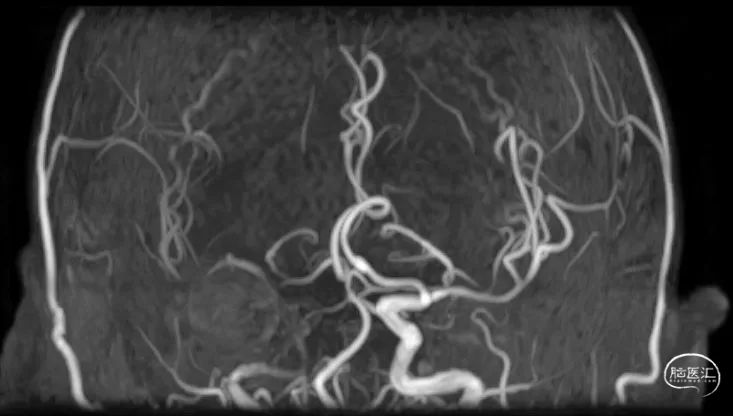

入院查体:神清,言语清晰,对答基本切题,双侧瞳孔等大圆形,对光反射灵敏,眼球向左、向上、向下运动不能,左侧鼻唇沟稍浅,口角右歪,伸舌左歪,左上肢肌力2-级,左下肢肌力3+级,右侧肢体肌力5级,双侧巴氏征阳性。NIHSS评分7分。头颅MRA:右侧颈内动脉闭塞。

为进一步评估梗死大小和颅内情况,磁共振显示颈内动脉闭塞,小的核心梗死。